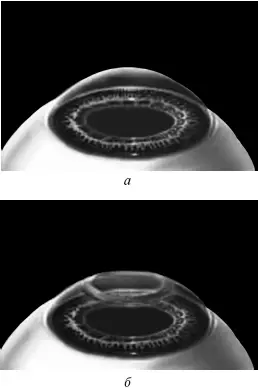

Ждем, когда закончится приживление лоскута к ложу. Эпителий цел и невредим. А значит, никаких болей. Около трех часов возможны слезотечение и светобоязнь. И все (рис. 9).

Рис. 9.Форма роговицы до проведения коррекции (а) и после коррекции близорукости (б) . Испарение нескольких микрон толщины роговицы привело к уменьшению ее кривизны в центре.

Иллюстрация с сайта Международного лазерного центра www.optics.ru